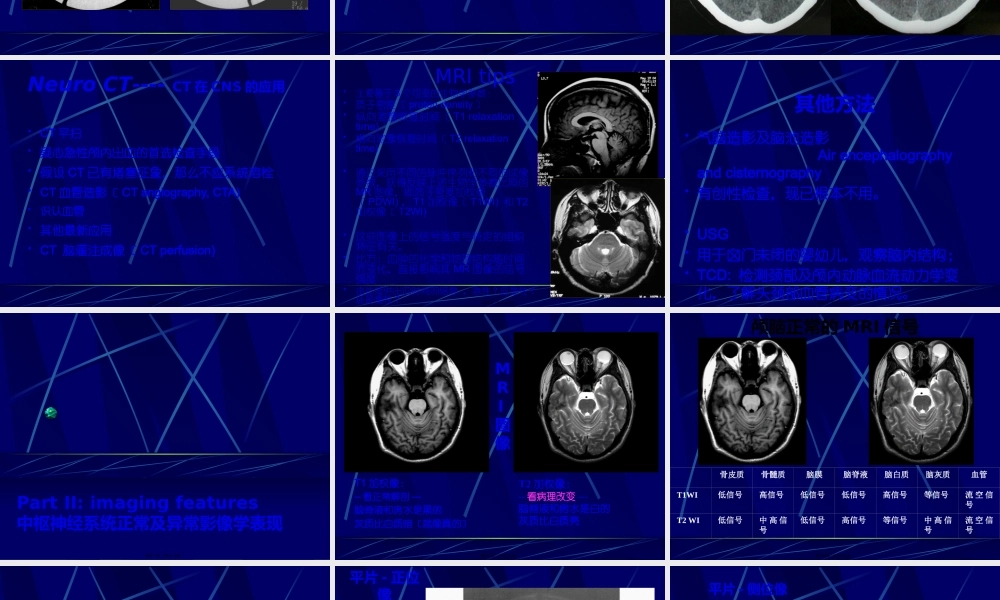

中枢神经系统正常及异常影像改变北京协和医院放射科第一页,共七十八页。中枢神经系统影像学技术颅骨平片脑血管造影脑CT脑磁共振第二页,共七十八页。头颅平片〔正侧位像〕第三页,共七十八页。头颅平片诊断价值有限•观察异物的存在和骨质结构的明显变化•显示骨折、肿瘤骨转移、网状内皮系统疾病、代谢性骨病、骨纤、畸形性骨炎等•观察颅骨骨折,有学者建议直接行CT•注意区分正常颅缝、血管沟和骨折线•有时可看见颅内钙化,如松果体钙化、肿瘤钙化等(中线钙化:松果体钙化、第三脑室脉络丛钙化、大脑镰钙化)•侧位可观察蝶鞍的形态,如扩大提示垂体瘤等,但不扩大也不能排除病变第四页,共七十八页。脑血管造影第五页,共七十八页。脑血管造影适应征•诊断脑动脉瘤、血管发育异常、血管闭塞•了解脑肿瘤的供血动脉•可同时行介入治疗•溶栓•Coil〔螺圈〕闭塞动脉瘤和血管畸形等•术前栓塞富血管性肿瘤如脑膜瘤•其他第六页,共七十八页。第七页,共七十八页。NeuroCT----CT在CNS的应用•CT平扫•疑心急性颅内出血的首选检查手段•假设CT已有堵塞征象,那么不应系统溶栓•CT血管造影〔CTangiography,CTA)•识认血管•其他最新应用•CT脑灌注成像〔CTperfusion)第八页,共七十八页。MRItips•主要基于3个可变的生物学参数:•质子密度〔protondensity〕•纵向驰豫恢复时间〔T1relaxationtime)•横向驰豫恢复时间〔T2relaxationtime)•通过采用不同的脉冲序列和不同的成像参数,获得反映上述生物学参数比照的MR图像,即质子密度加权像〔PDWI)、T1加权像〔T1WI)和T2加权像〔T2WI)•这些图像上的信号强度与特定的组织特征有关。•比方:血肿的化学和物理结构随时间而变化,直接影响其MR图像的信号强度•由此提供出血时间的信息,急性?亚急性?还是慢性?第九页,共七十八页。其他方法•气脑造影及脑池造影Airencephalographyandcisternography•有创性检查,现已根本不用。•USG•用于囟门未闭的婴幼儿,观察脑内结构;•TCD:检测颈部及颅内动脉血流动力学变化,了解头颈部血管病变的情况。第十页,共七十八页。PartII:imagingfeatures中枢神经系统正常及异常影像学表现第十一页,共七十八页。MRI图像T1加权像:--看正常解剖---脑脊液和房水是黑的灰质比白质暗〔就像真的〕T2加权像:--看病理改变---脑脊液和房水是白的灰质比白质亮第十二页,共七十八页。骨皮质骨髓质脑膜脑脊液脑白质脑灰质血管T1WI低信号高信号低信号低信号高信号等信...

3、如文档内容存在违规,或者侵犯商业秘密、侵犯著作权等,请点击“违规举报”。

碎片内容